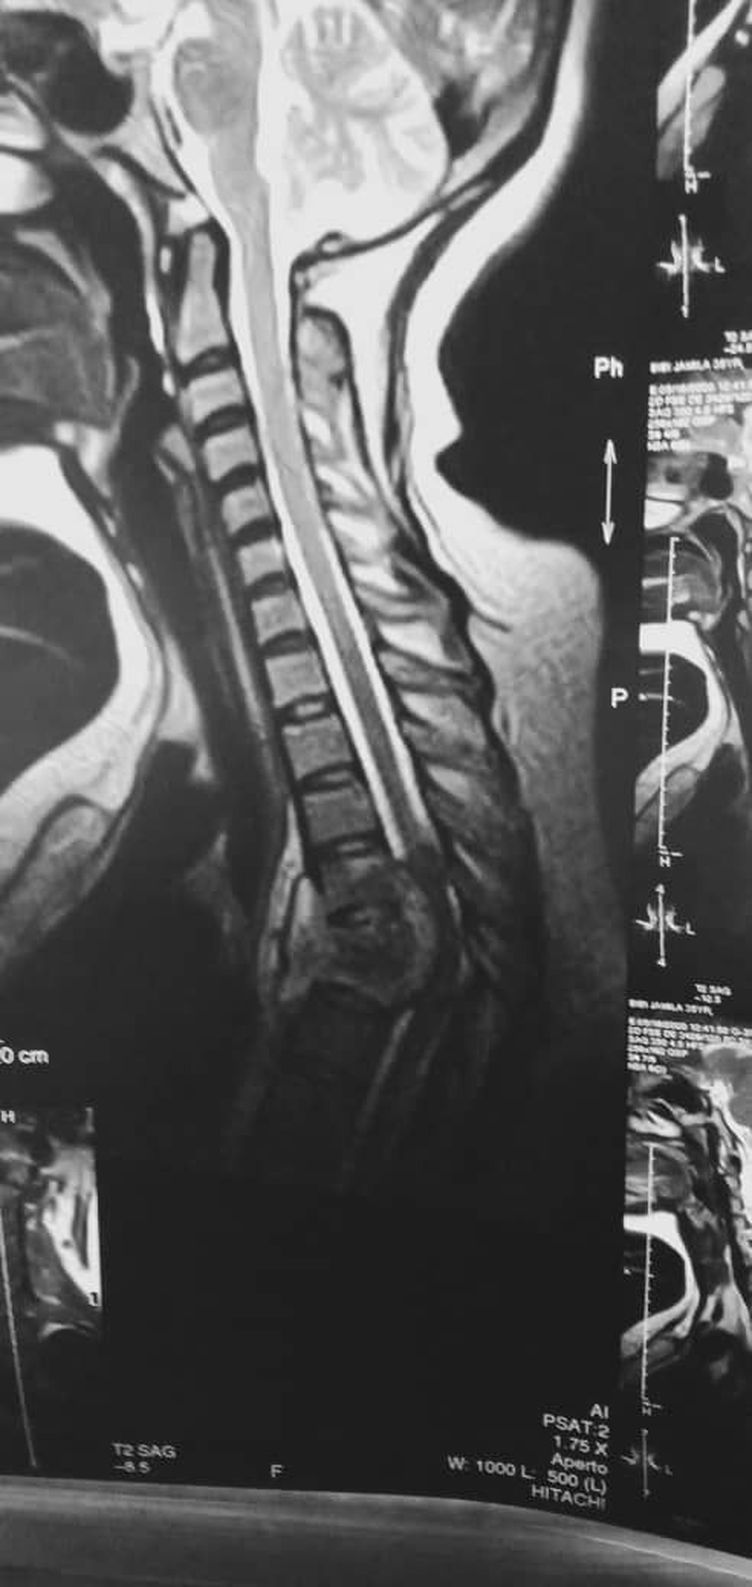

diagnosis?

It appears to be a tumor in the spinal column.